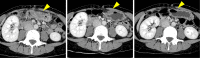

A 44-year-old woman presented to our hospital with abdominal pain. Abdominal ultrasonography and computed tomography showed a mass-like change in the lesser omentum between the liver and stomach. Esophagogastroduodenoscopy revealed a submucosal tumor-like change, and endoscopic ultrasonography (EUS) revealed that the mass was located outside of the stomach wall. We performed EUS fine-needle aspiration and diagnosed panniculitis of the lesser omentum. Based on these findings, we suggest that mass-like lesions in the lesser omentum and submucosal tumor-like changes in the anterior wall on the lesser curvature side of the stomach be evaluated for the possibility of panniculitis of the lesser omentum.